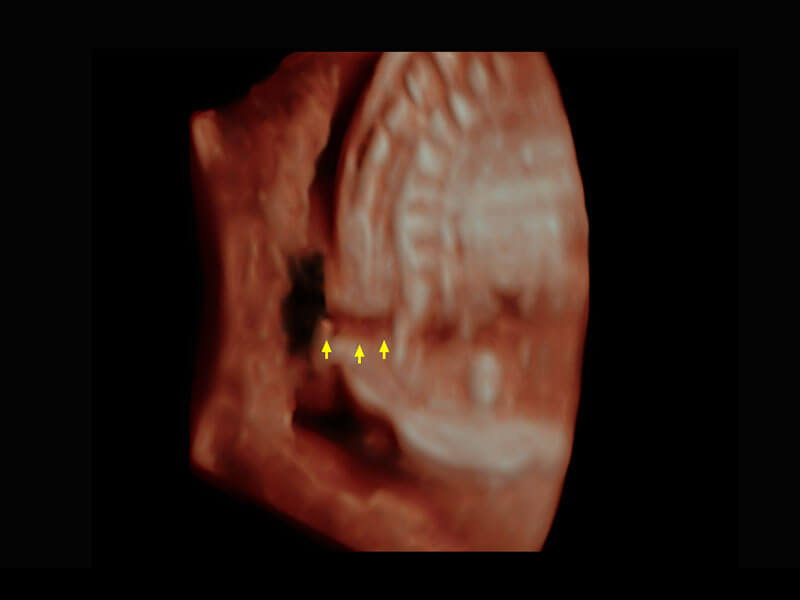

P60搭载一系列胎儿心脏成像技术,实现精细的胎儿心脏评估。

四腔切面

四腔心血流

胎心容积成像